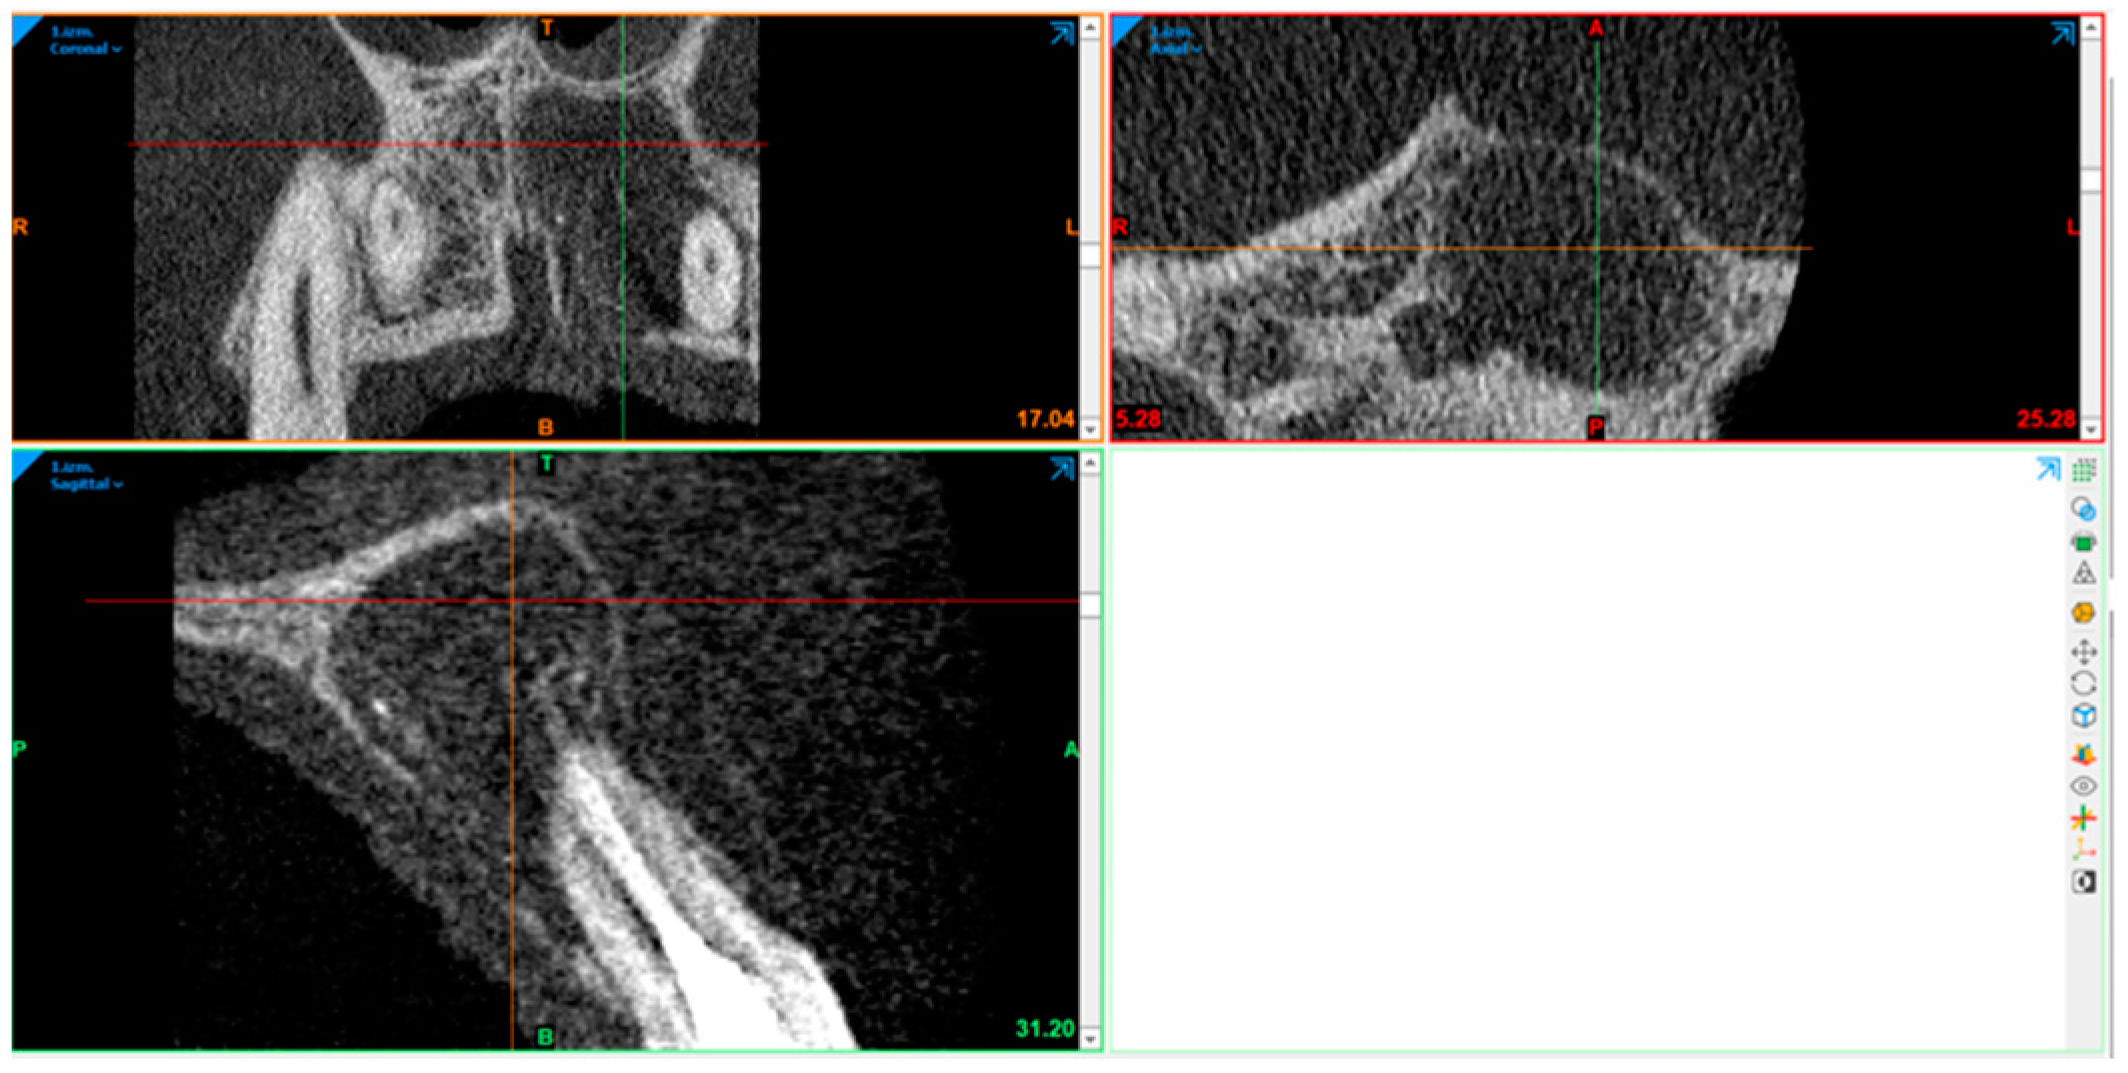

2.10. Radiography Acquisition: Volumetric Assessment

2.11. Statistical Analysis